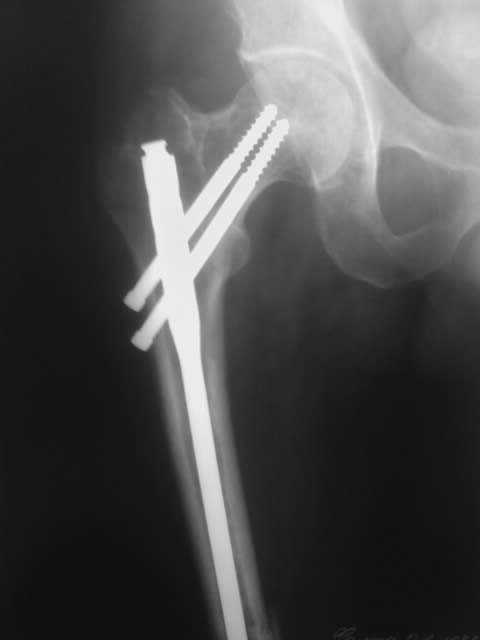

Был меж вертельный и оскольчатый перелом бедра, сделали остеосинтез,прошло 5 месяцев,не сращение.предлагают убрать нижний болт и сделать пластику.на что согласиться?

На мой взгляд, представленный план неоптимален, и может создать больше проблем, чем решить.

Стержень тонкий, на уровне нижнего перелома нестабильность, в этих условихя пластику делать бесперспективно - из-за подвижности не прорастут сосуды, соответственно, не приживет трансплантат.

И при закрытом интрамедуллярном остеосинтезе вообще пластики делать ни к чему. Здесь нужно убрать этот гвоздь, рассверлить канал и ввести гвоздь больше диаметром. И заереть его внизу понадежнее, винтами большего диаметра и не короткими, как сейчас. Вверху - динамически и с компрессией. Тут же можно будет ходить без ограничения нагрузки.

После реостеосинтез с рассверливанием обычно срастается. Про осколок думать не надо, пусть остается, где есть. Должно срастись хотя бы по передней поверхности. С гвоздем внутри запас времени будет очень большой, риск повторного перелома из-за асимметричного сращения отсуствует.

Если не сросся вертельный перелом, это даже хорошо, т.к. можно было бы исправить положение и там. Вы показали только одну проекцию, полноценно оценить сращение не получится.